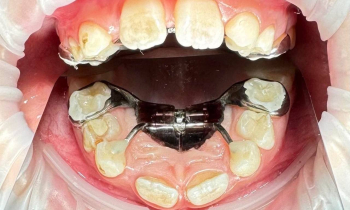

Наш ортодонт Евгений Владиславович Алексеев использует в своей работе не только стандартные общепринятые методики, но и самые современные, такие как аппарат Марко Роса